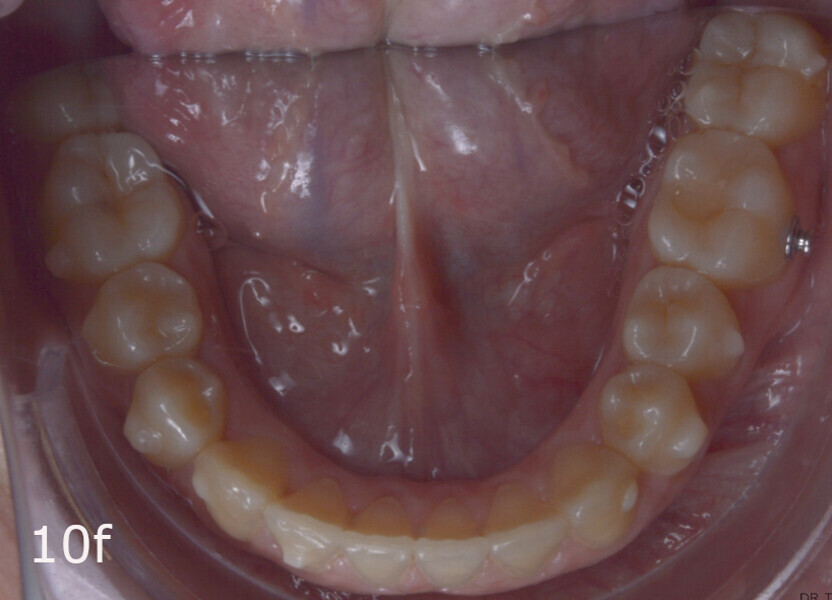

The treatment objectives included closing the anterior open bite, achieving a bilateral Angle Class I relationship and a proper overjet and overbite, correcting the midline discrepancies, and achieving a profile harmonisation. The treatment plan consisted of orthodontic camouflage treatment with asymmetric distalisation in three of the four quadrants using Invisalign aligners (Align Technology) and third molar extraction. The Invisalign Comprehensive package was chosen, and 63 pairs of aligners were used (Figs. 7–10). Each aligner was worn for 20 hours a day for one week each. The use of Class III elastics on both sides was indicated. Afterwards, ten refinement aligners were needed to improve the interdigitation on the right side (Figs. 11 & 12).

The total treatment time was 15 months. An Angle Class I relationship was established along with adequate anterior and canine guidance, establishing a functional occlusion. This not only ensures optimal masticatory function but also protects the teeth and the temporomandibular joint from excessive force. Maxillary and mandibular fixed retention were installed at the end of the treatment (Figs. 13–19).